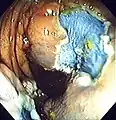

An advantage of colonoscopy over X-ray imaging or other less invasive tests is the ability to perform therapeutic interventions during the test. A polyp is a growth of excess of tissue that can develop into cancer. If a polyp is found, for example, it can be removed by one of several techniques. A snare device can be placed around a polyp for removal. Even if the polyp is flat on the surface it can often be removed. For example, the following shows a polyp removed in stages:

Polyp is identified.

A sterile solution is injected under the polyp to lift it away from deeper tissues.

A portion of the polyp is now removed.

The polyp is fully removed.